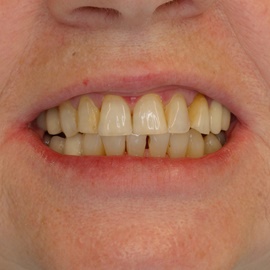

Bezzębie całkowite górne. Początkowo wykonane na mieście mosty całoceramiczne wydawały sie sukcesem, ale po roku pojawiły sie obrzęki i krwawienie z dziąseł. Pacjentka zgłosiła się do leczenia. Usunięto wszystkie zęby w szczęce. Sterowana regeneracja tkanek kości wyrostka, modelowanie kształtu i objętości tkanek miękkich, mosty porcelanowe przykręcane do implantów. Zadowalający wynik anatomiczny i estetyczny.